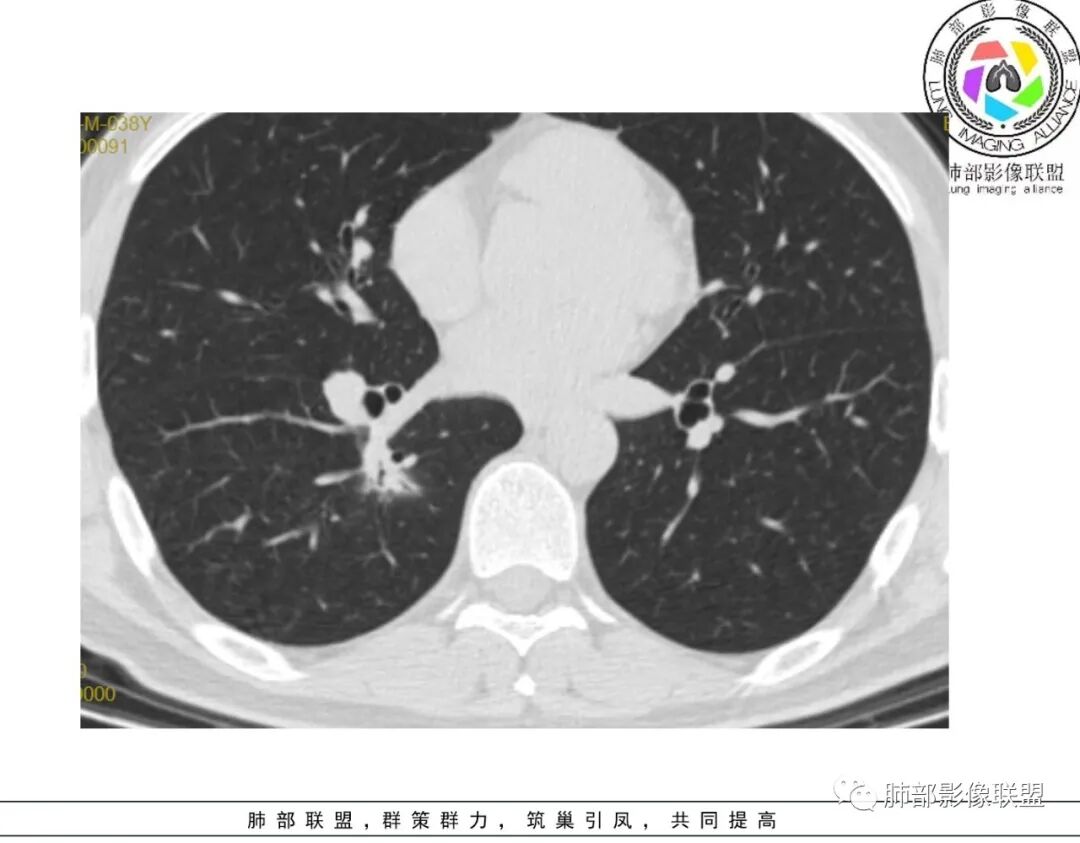

谢加平:左肺上叶和右肺下叶见多发散在性斑块病灶,边界清楚,部分见U形凹陷和刀切征,周围见模糊晕征,近胸膜下分布和蘑菇兄弟特点,累及左肺上叶上舌段支气管牵拉性扩张,前后13天复查整体病灶吸收不明显,有机化趋势表现,首选炎性肉芽肿(隐球菌感染?),请结合隐球菌荚膜抗原检查。

蓝天白云:两肺多发斑片状影,晕,内见扩张支气管影,可见直边,轻度延迟强化,纵隔肿大淋巴结,考虑炎性肉芽肿,隐球,淋巴瘤。

丽:双肺散在片状及结节状高密度影,边缘模糊,支气管穿行,走形僵硬,不均匀强化,考虑:OP,鉴别隐球菌,淋巴瘤。

小兜:男性,39岁,3周前劳累受凉史,次日至三亚开始咳嗽咳痰,入院时自述症状减轻。CT示双肺多发斑片影,部分病灶内部支气管壁增厚扩张穿行,平扫密度均匀,增强未见明显坏死,治疗前后部分病灶略吸收。实验室检查白细胞血沉轻度增高。考虑隐球菌感染可能,鉴别类鼻疽,淋巴瘤。

巴伟:双肺多发斑片影,边缘模糊,有晕,有支气管扩张,轻度强化,先考虑感染性病变,隐球,鉴别淋巴瘤。

穿越七海的风:双肺多发结节斑片影,边缘模糊有晕,亚急性病程,咳嗽黄痰,周围渗出,支气管张扩,胸膜增厚,复查病灶略有吸收,考虑感染性病变,隐球菌?

2、影像资料:双肺多发的小结节、斑片状及不规则型的实性病灶,周围有晕,沿支气管血管束分布,部分的病灶周围可见磨玻璃样影、支气管的扩张以及小的空洞。增强扫描病灶,轻度强化内部见支气管造影征。部分的病灶,支气管有扩张,内壁凹凸不平的改变,纵隔淋巴结未见肿大。病灶整体的形态还是多样化,部分位于胸膜下。